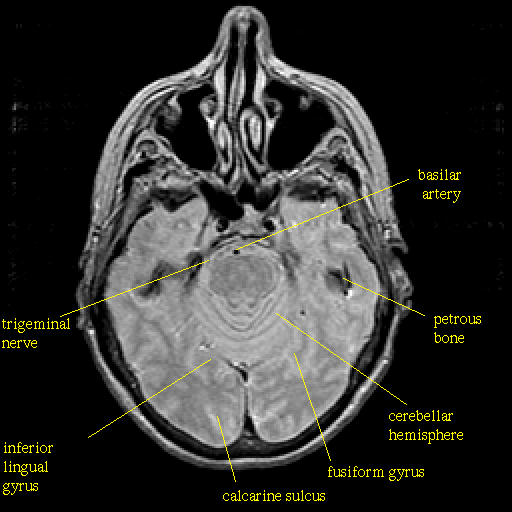

Proton density-weighted structural MR: Slice 17

Pointers

Labeled